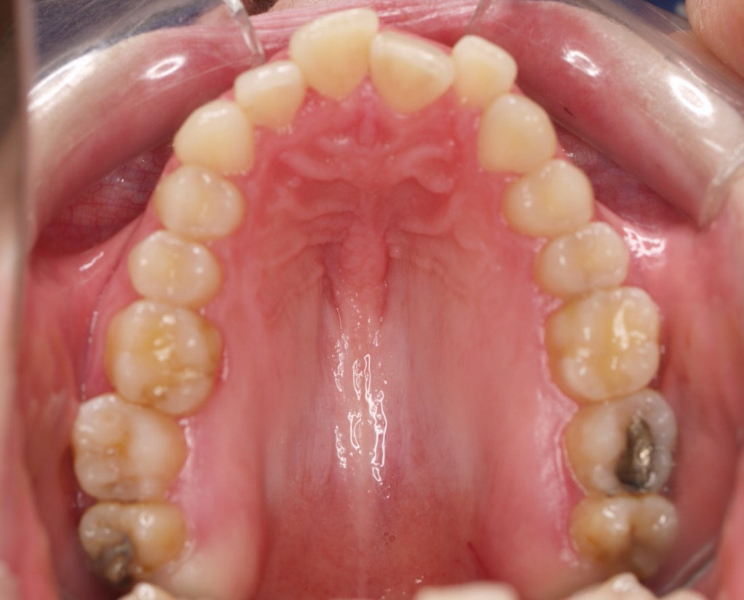

Premolar mandibular incluido + fenestración

45 incluido

Radiografía de final de tratamiento